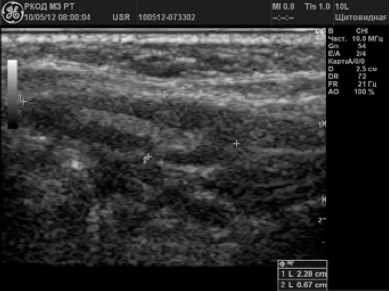

В 58 (38,2%) случаях было заподозрено метастатическое поражение лимфатических узлов. Измененные ЛУ имели размеры от 6 до 65 мм; 72,4% лимфатических узлов имели шарообразную форму, П/ПЗ2,0; 17,3% — неправильную форму в виде конгломератов. У 24 (41,4%) пациентов были выявлены единичные измененные лимфоузлы; у 34 (58,6%) — множественные. У 79,3% лимфоузлов отсутствовала дифференциация на кору и ворота; у 20,7% — ворота определялись в виде мелкого гиперэхогенного включения. 70,8% лимфатических узлов были гипоэхогенными (рис. 3); 12% — анэхогенными; 17,2% — неоднородную структуру с участками повышенной и пониженной эхогенности, с жидкостными включениями и кальцинатами (рис. 4).

Рисунок 3.

Метастазы в лимфоузлы шеи при раке щитовидной железы